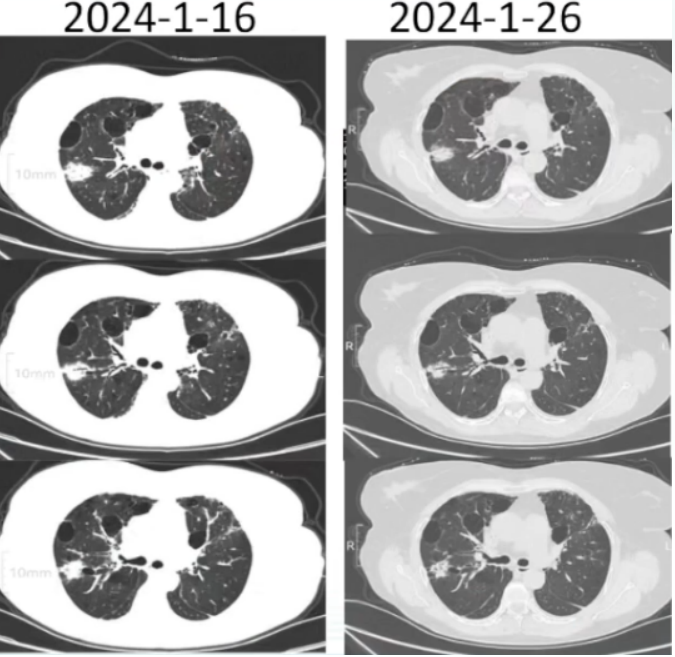

9. 胸部CT2024-01-26

胸廓基本对称,双肺内示片状及网格样高密度影116片未见明显改变,各主支气管开口通畅,双肺内散在低密度影纵隔内未见明显肿大淋巴结(图2)

2  患者胸部CT对比